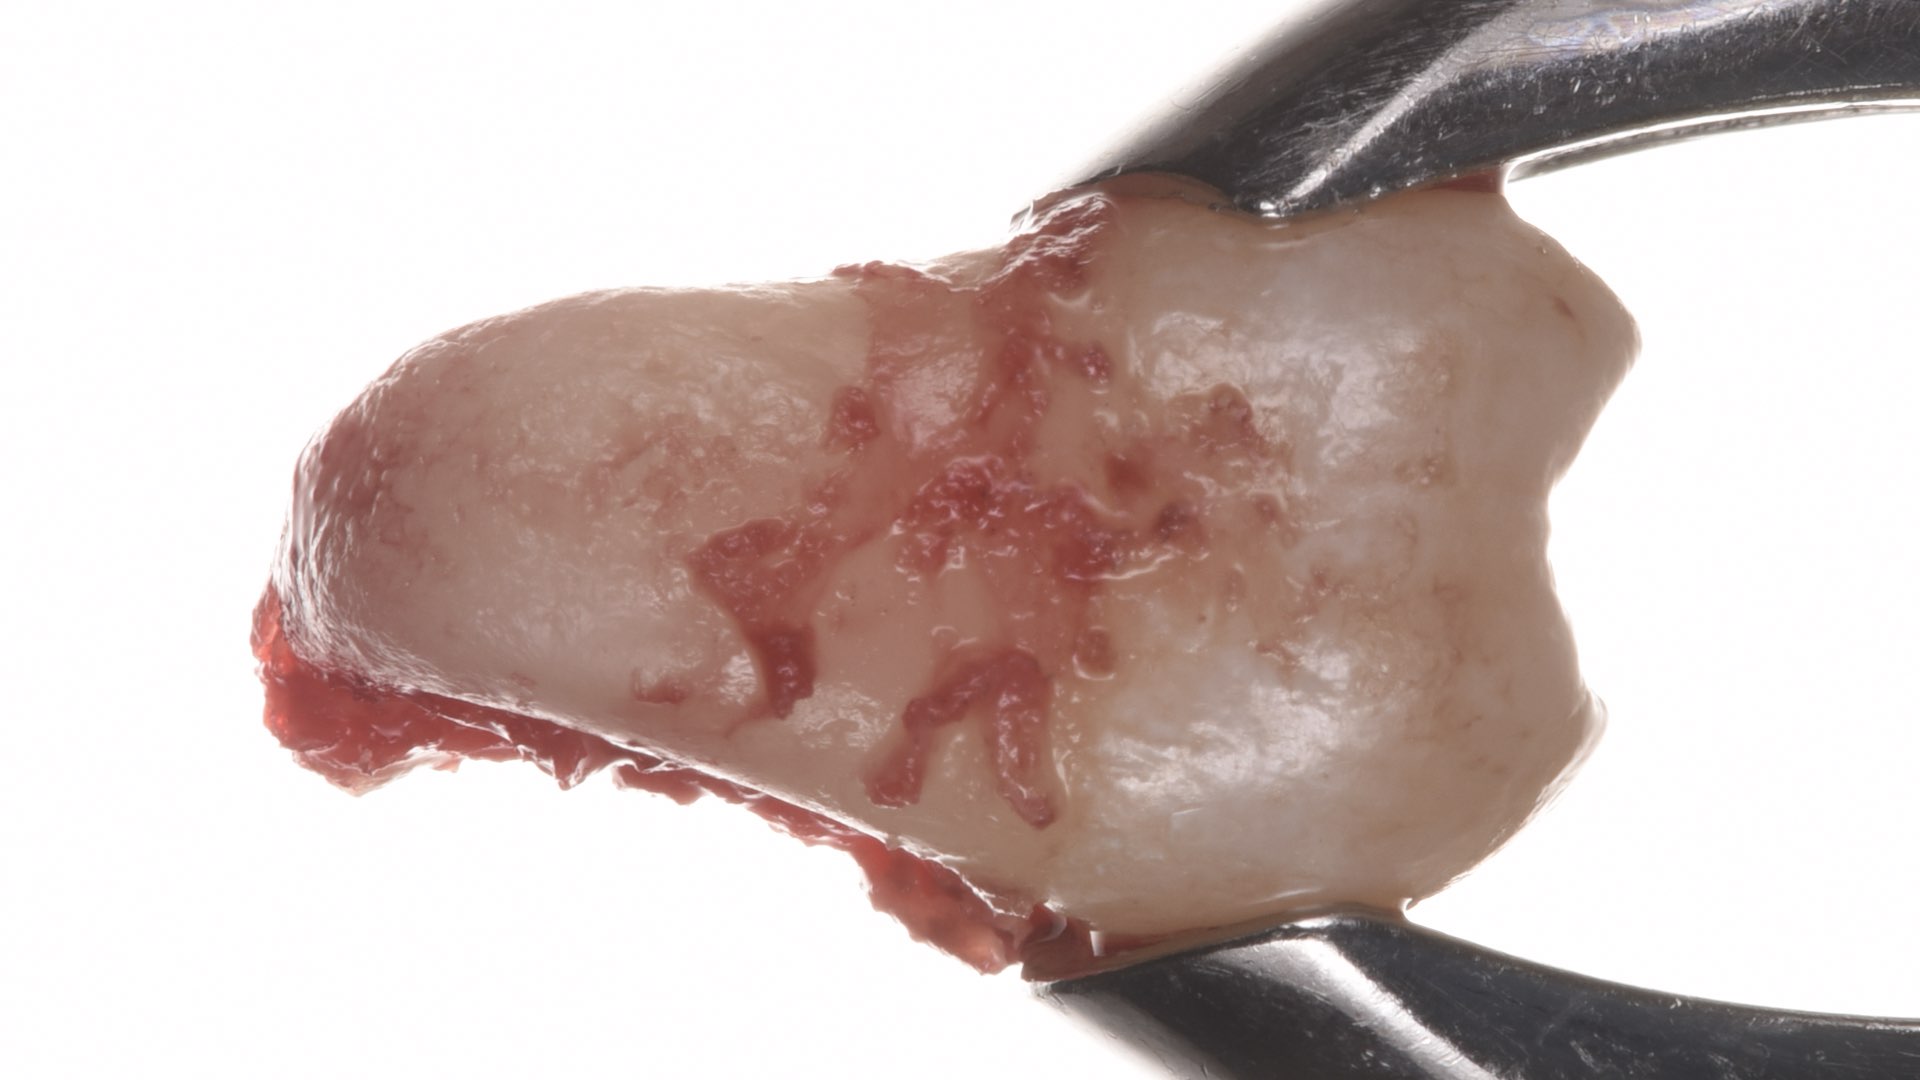

- Practicing on true anatomy models, pig jaws and dental models

- How to split teeth with multiple radices

- How to gently remove some alveolar bone to facilitate the extraction

- How to properly extract the tooth

- How to preserve as much bone as possible

- How to clean the alveolar socket